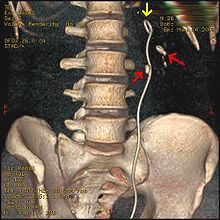

Imaging studies

Calcium-containing stones are relatively radiodense, and they can often be detected by a traditional radiograph of the abdomen that includes the kidneys, ureters, and bladder (KUB film).[28] Some 60% of all renal stones are radiopaque.[29][30] In general, calcium phosphate stones have the greatest density, followed by calcium oxalate and magnesium ammonium phosphate stones. Cystine calculi are only faintly radiodense, while uric acid stones are usually entirely radiolucent.[31]

Where available, a noncontrast helical CT scan with 5 millimeters (0.20 in) sections is the diagnostic modality of choice in the radiographic evaluation of suspected nephrolithiasis.[3][26][29][32][33] All stones are detectable on CT scans except very rare stones composed of certain drug residues in the urine,[28] such as from indinavir.

Where a CT scan is unavailable, an intravenous pyelogram may be performed to help confirm the diagnosis of urolithiasis. This involves intravenous injection of a contrast agent followed by a KUB film. Uroliths present in the kidneys, ureters or bladder may be better defined by the use of this contrast agent. Stones can also be detected by a retrograde pyelogram, where a similar contrast agent is injected directly into the distal ostium of the ureter (where the ureter terminates as it enters the bladder).[29]